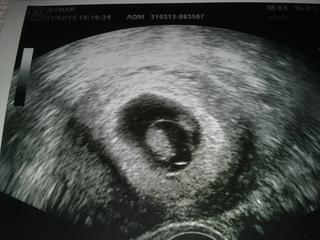

@eliss2 Nestraš 🙂 Dr. mluvila jen o jednom. To druhý co myslíš tam vpravo nahoře je žloutkový vak nebo jak se to jmenuje 🙂 Srdíčko tam taky blikalo,ale to tady na fotce nejde vidět.

Hele tekutina, netekutina, hlavní je, že tam plave lochneska 😉